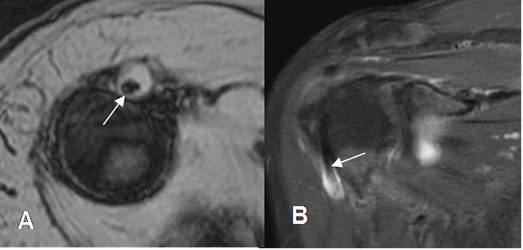

Fig 151. Tenosinovitis de la cabeza larga del bíceps.

A: RM axial en FFE y B: RM coronal en STIR. Tendón de la cabeza larga del biceps completamente rodeado por líquido, por tenosinovitis.